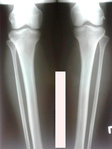

Исходник - 43 года.Астана.

Дата операции -21.11.2018г.

IMG-20181119-WA0023.jpg

IMG-20181119-WA0025.jpg